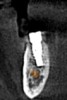

(7.) Postoperative CBCT images confirming implant placement according to the digital plan.

Figure 7

(8.) Postoperative CBCT images confirming implant placement according to the digital plan.

Figure 8

On the day of surgery, a prefabricated tooth-borne splint with an extraoral extension was placed on the patient's contralateral arch and secured with a cold-cure hard relining material. The splint was uniquely designed so that a "breakaway" technique could be used to remove it upon completion of the case. Next, a resin attachment with seven round metal beads, called a fiducial array, was magnetically attached to the splint extension (Figure 6). A new CBCT scan was then taken to capture the fiducial array and relate the splint to the patient's anatomy. After a calibration process was completed to ensure the accuracy of the robotic guidance arm, it was attached to the oral splint and secured. The guidance arm allows the system to identify the patient's anatomy, detect movement, and move with the patient. Profound anesthesia was achieved, and tooth No. 12 was extracted utilizing an atraumatic flapless technique. Next, an implant bur was placed into the robotic handpiece and measured, and accuracy was again confirmed using a predetermined landmark on tooth No. 11. The implant drilling protocol was then completed using the robotic handpiece. Drilling angle, position, and depth are constrained to the plan by the robotic arm, which uses haptic guidance to limit the movement of the handpiece to the proper position by providing physical resistance and feedback during the drilling process. The monitor provides visual navigation and confirmation of the correct angle, position, and depth; however, the surgeon may complete the drilling protocol by viewing either the monitor or the patient directly. After the same robotic protocol was used to place the implant into the osteotomy, allogenic bone was injected and condensed into the osseous defect and a temporary cylinder was placed in preparation for an immediate nonloaded provisional crown. A postoperative CBCT scan confirmed that the dental implant had been placed in accordance with the virtual plan (Figure 7 and Figure 8).